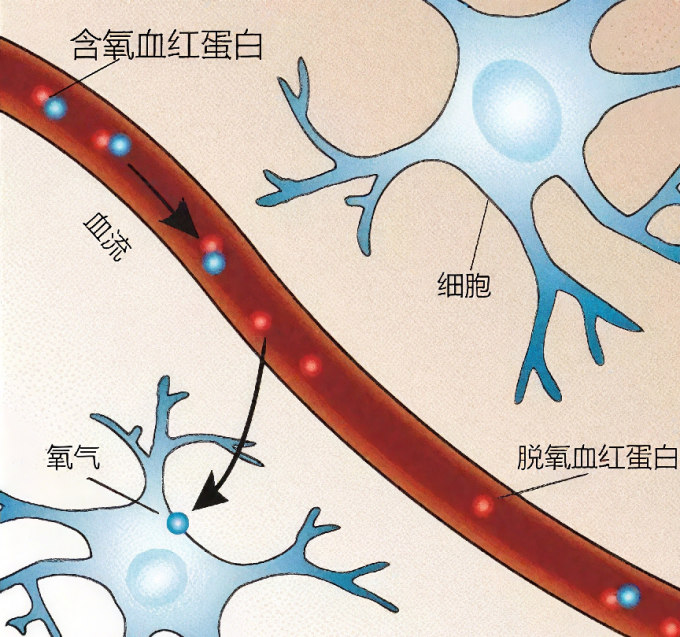

当大脑的某个区域处于活跃状态时,它会需要更多能量,导致血流量的增加。fMRI 能极其灵敏地这种血流变化带来的细微信号差异,绘制出大脑功能图像。

大脑活跃时的血流变化

通过探测不同任务状态下大脑的血氧变化,磁共振技术得以标识忙碌的脑区。这为研究大脑工作机制,理解大脑的各种功能提供了强大工具。